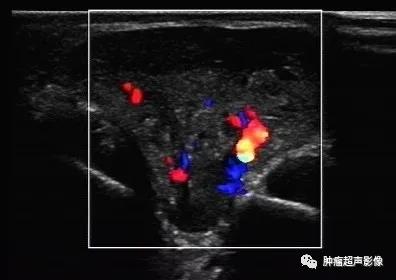

5、 CDFI:大部分血流信号较丰富,一般肿瘤大小与血流丰富有一定关系:较大的血流信号丰富,较小的肿瘤可无血流信号。

病理证实的血管平滑肌瘤,女45,下肢、单发、可移动、疼痛八年的结节,超声表现为皮下边界清的椭圆形低回声肿块,包膜完整,血流丰富,符合典型血管平滑肌瘤。

病理证实的血管平滑肌瘤,下肢、单发、可移动的疼痛结节,超声表现为皮下边界清的椭圆形低回声肿块(内见无回声),包膜完整,血流丰富,符合典型血管平滑肌瘤。